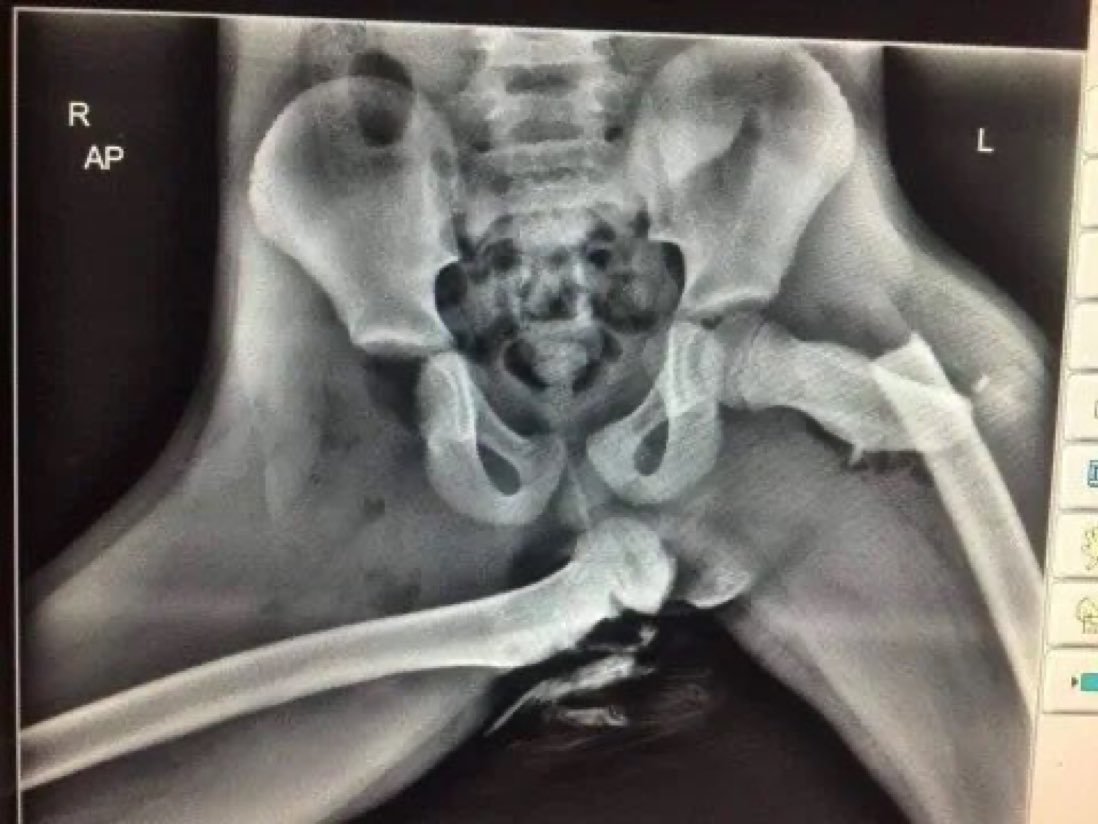

Pas de ceinture attachée..